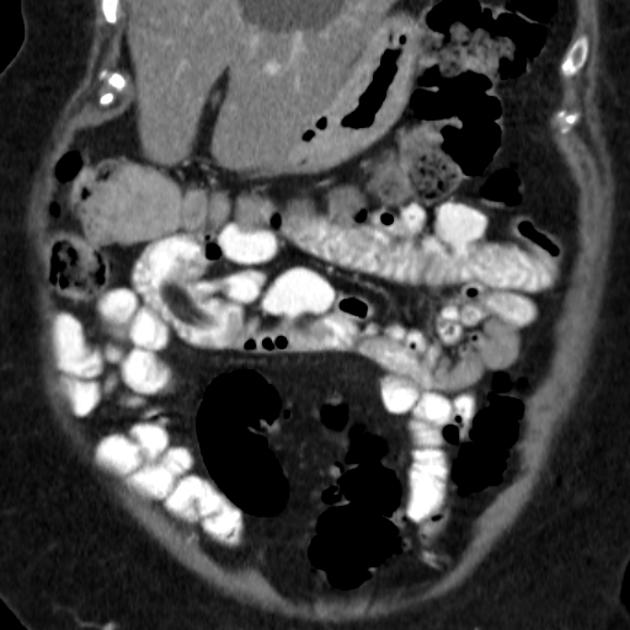

Lipome de

intestin grele : :Masse ovoide a bord lisse et

a hypodense de intestin . Image TDM en coupe coronal |